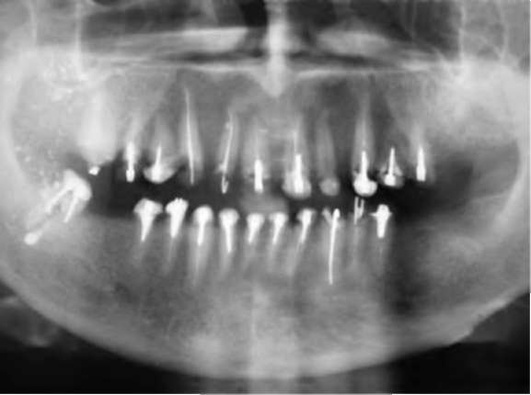

Вокруг участка разрежения можно видеть плотное губчатое вещество костной ткани. При обострении процесса гранулема может принимать нечёткие контуры. Благоприятным исходом при своевременном и правильно проведённом лечении считают регрессию очага деструкции и восстановление костной ткани. Отсутствие или неправильное лечение могут привести к увеличению очага воспаления и резорбции кости с развитием радикулярной кисты (рис. 13-9).

image

Рис. 13-9. Внутриротовые рентгенограммы: а - деструкция костной ткани у верхушки корня зуба 35 (как исход некачественного эндодонтического лечения); б - деструкция костной ткани у верхушки зуба 22

Рентгенологическую картину характеризует деструкция тканей у верхушки корня, где образуются различных размеров очаги разрежения костной ткани без четких границ (рис. 13-10).

Рис. 13-10. Внутриротовая рентгенограмма. Деструкциия костной ткани с нечеткими контурами у верхушек корней зубов 14, 15